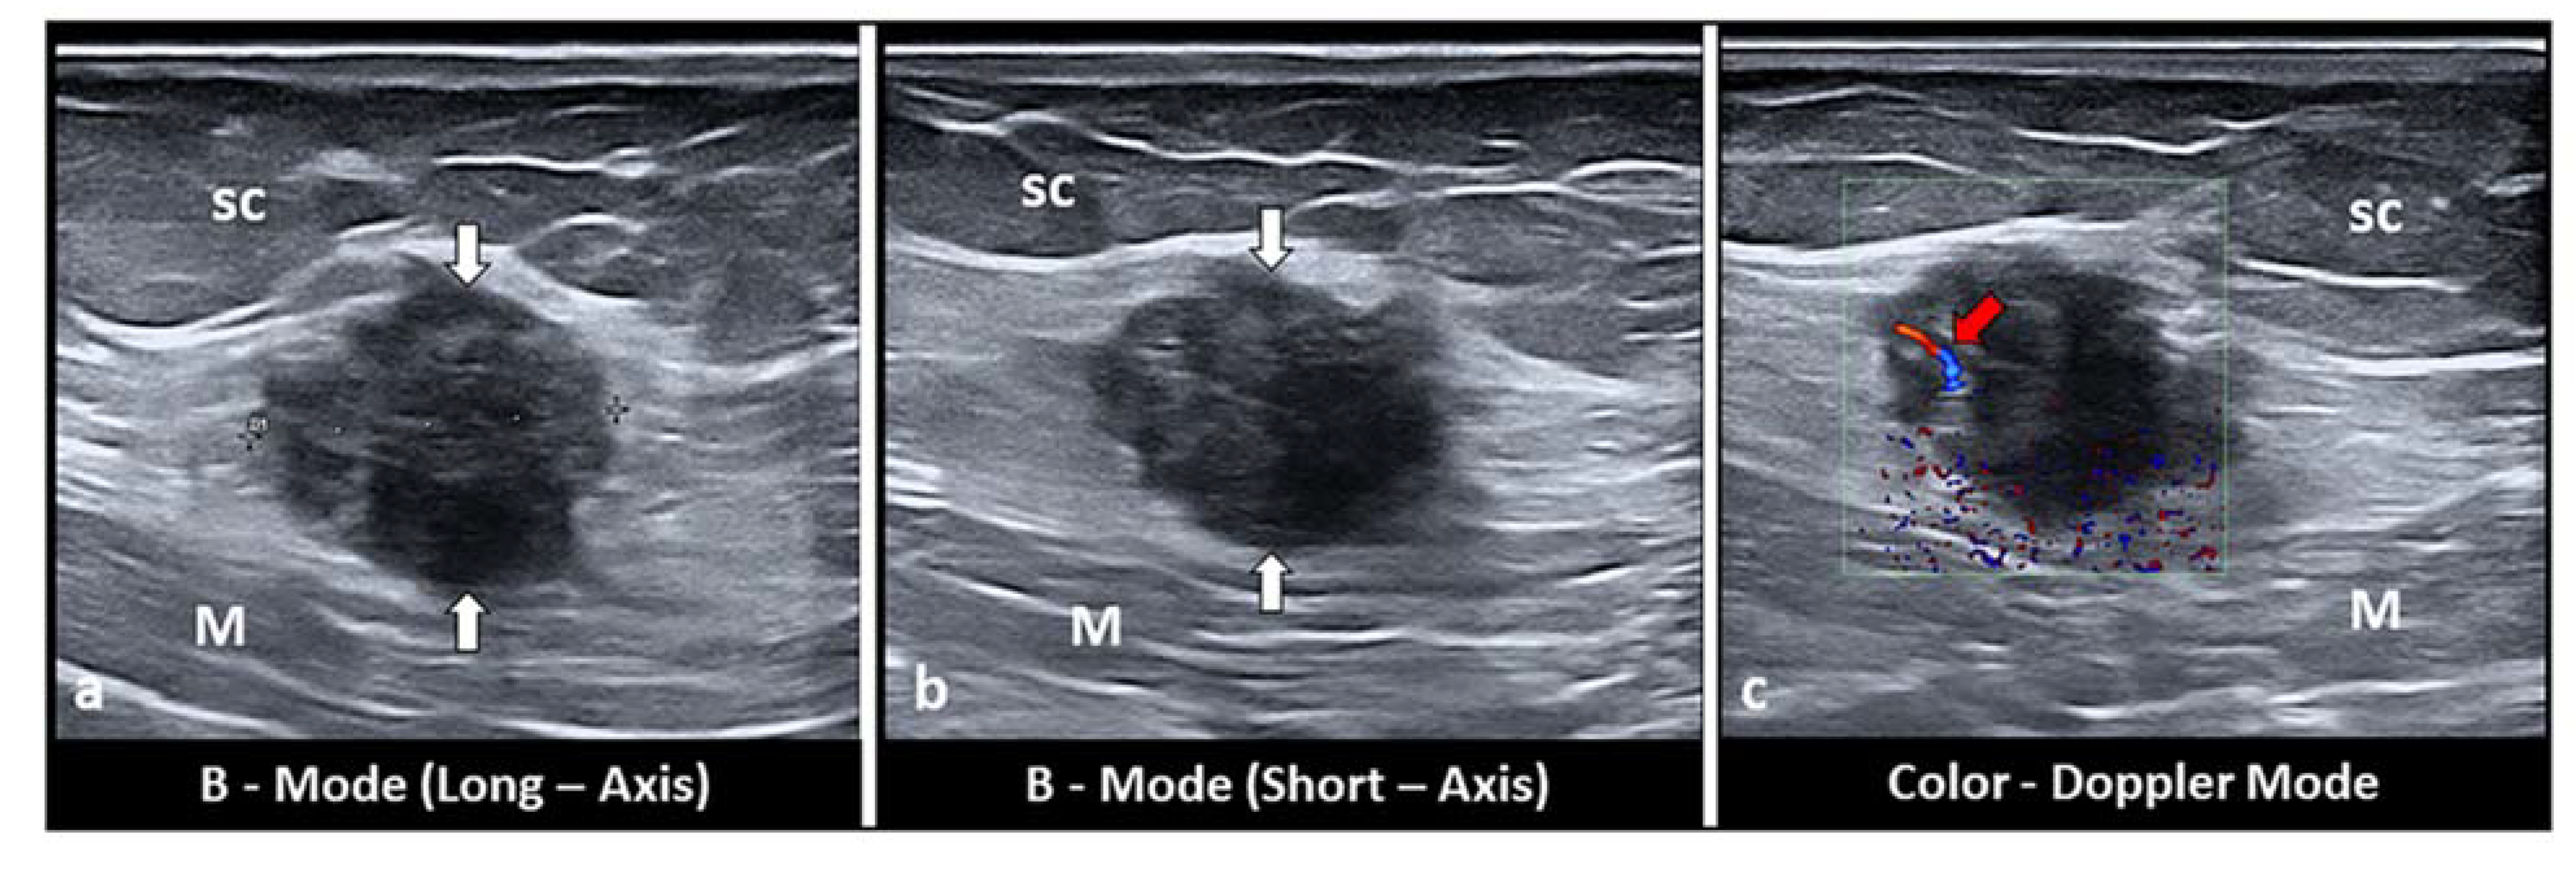

4. Subcutaneous Endometriosis